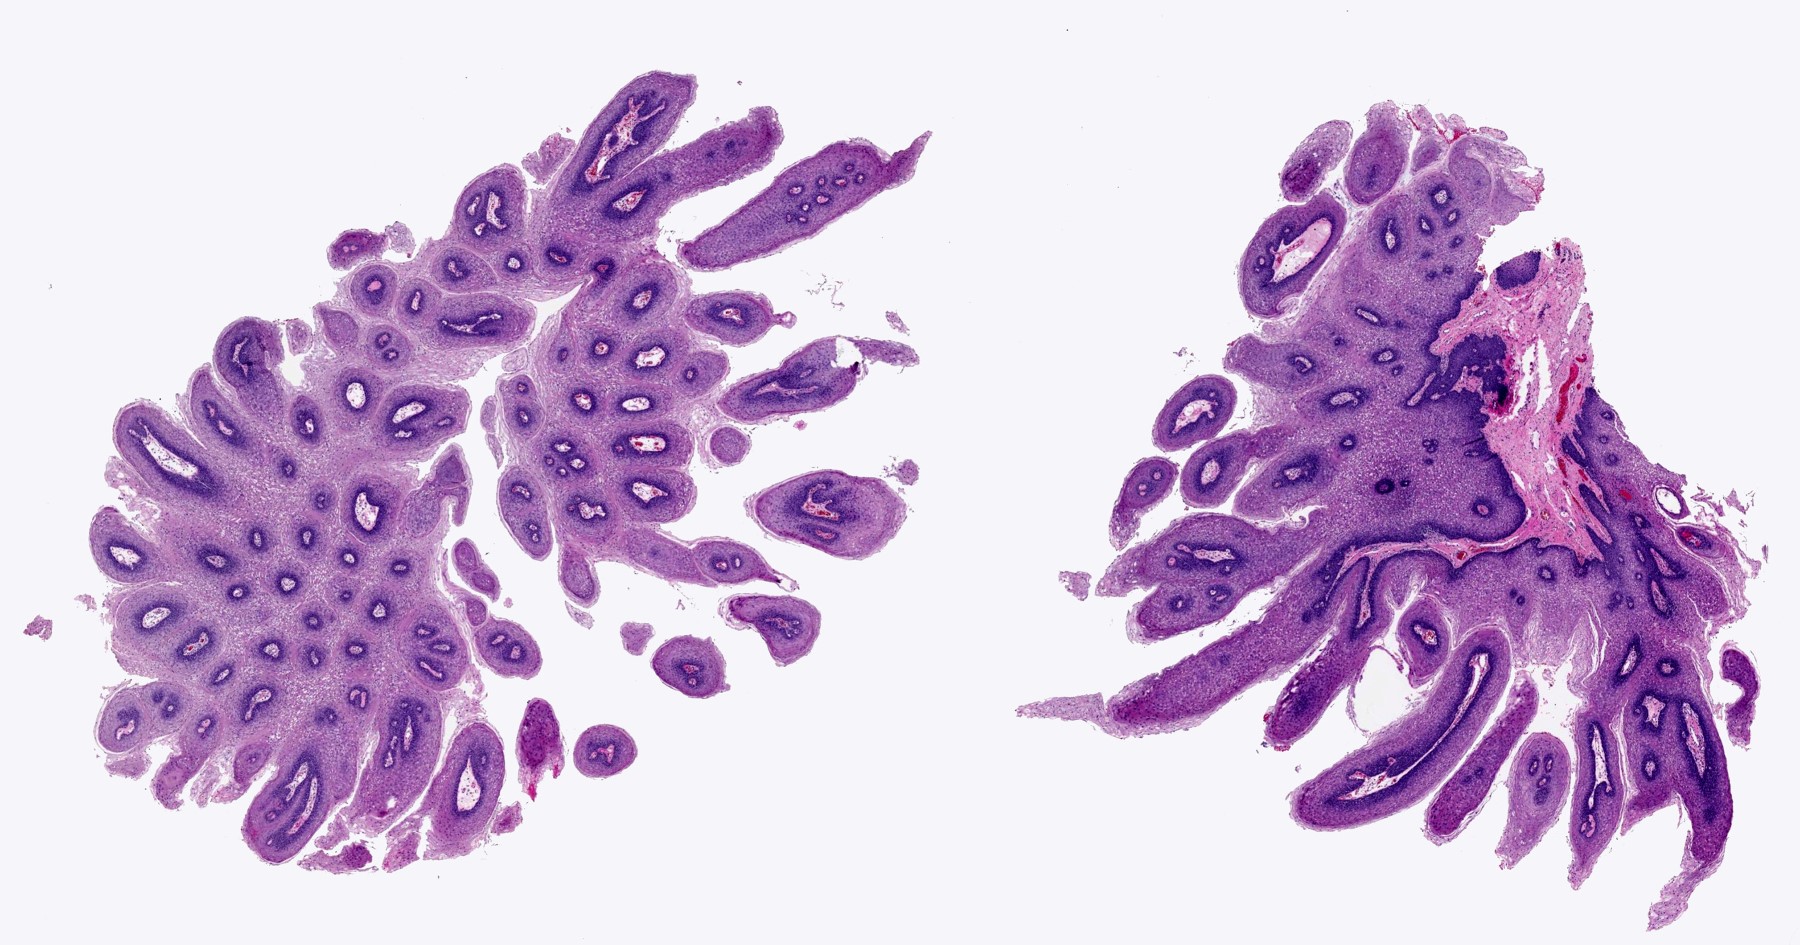

Microscopic (histologic) description

- Finger-like projections or multiple fronds with a central fibrovascular core, covered by benign hyperplastic stratified squamous epithelium

- Basal and parabasal hyperplasia

- Increased mitotic figures in the basal and parabasal layers

- Koilocytic changes in upper layer: may be pronounced or subtle

- Surface keratinization: absent to minimal

Microscopic (histologic) images